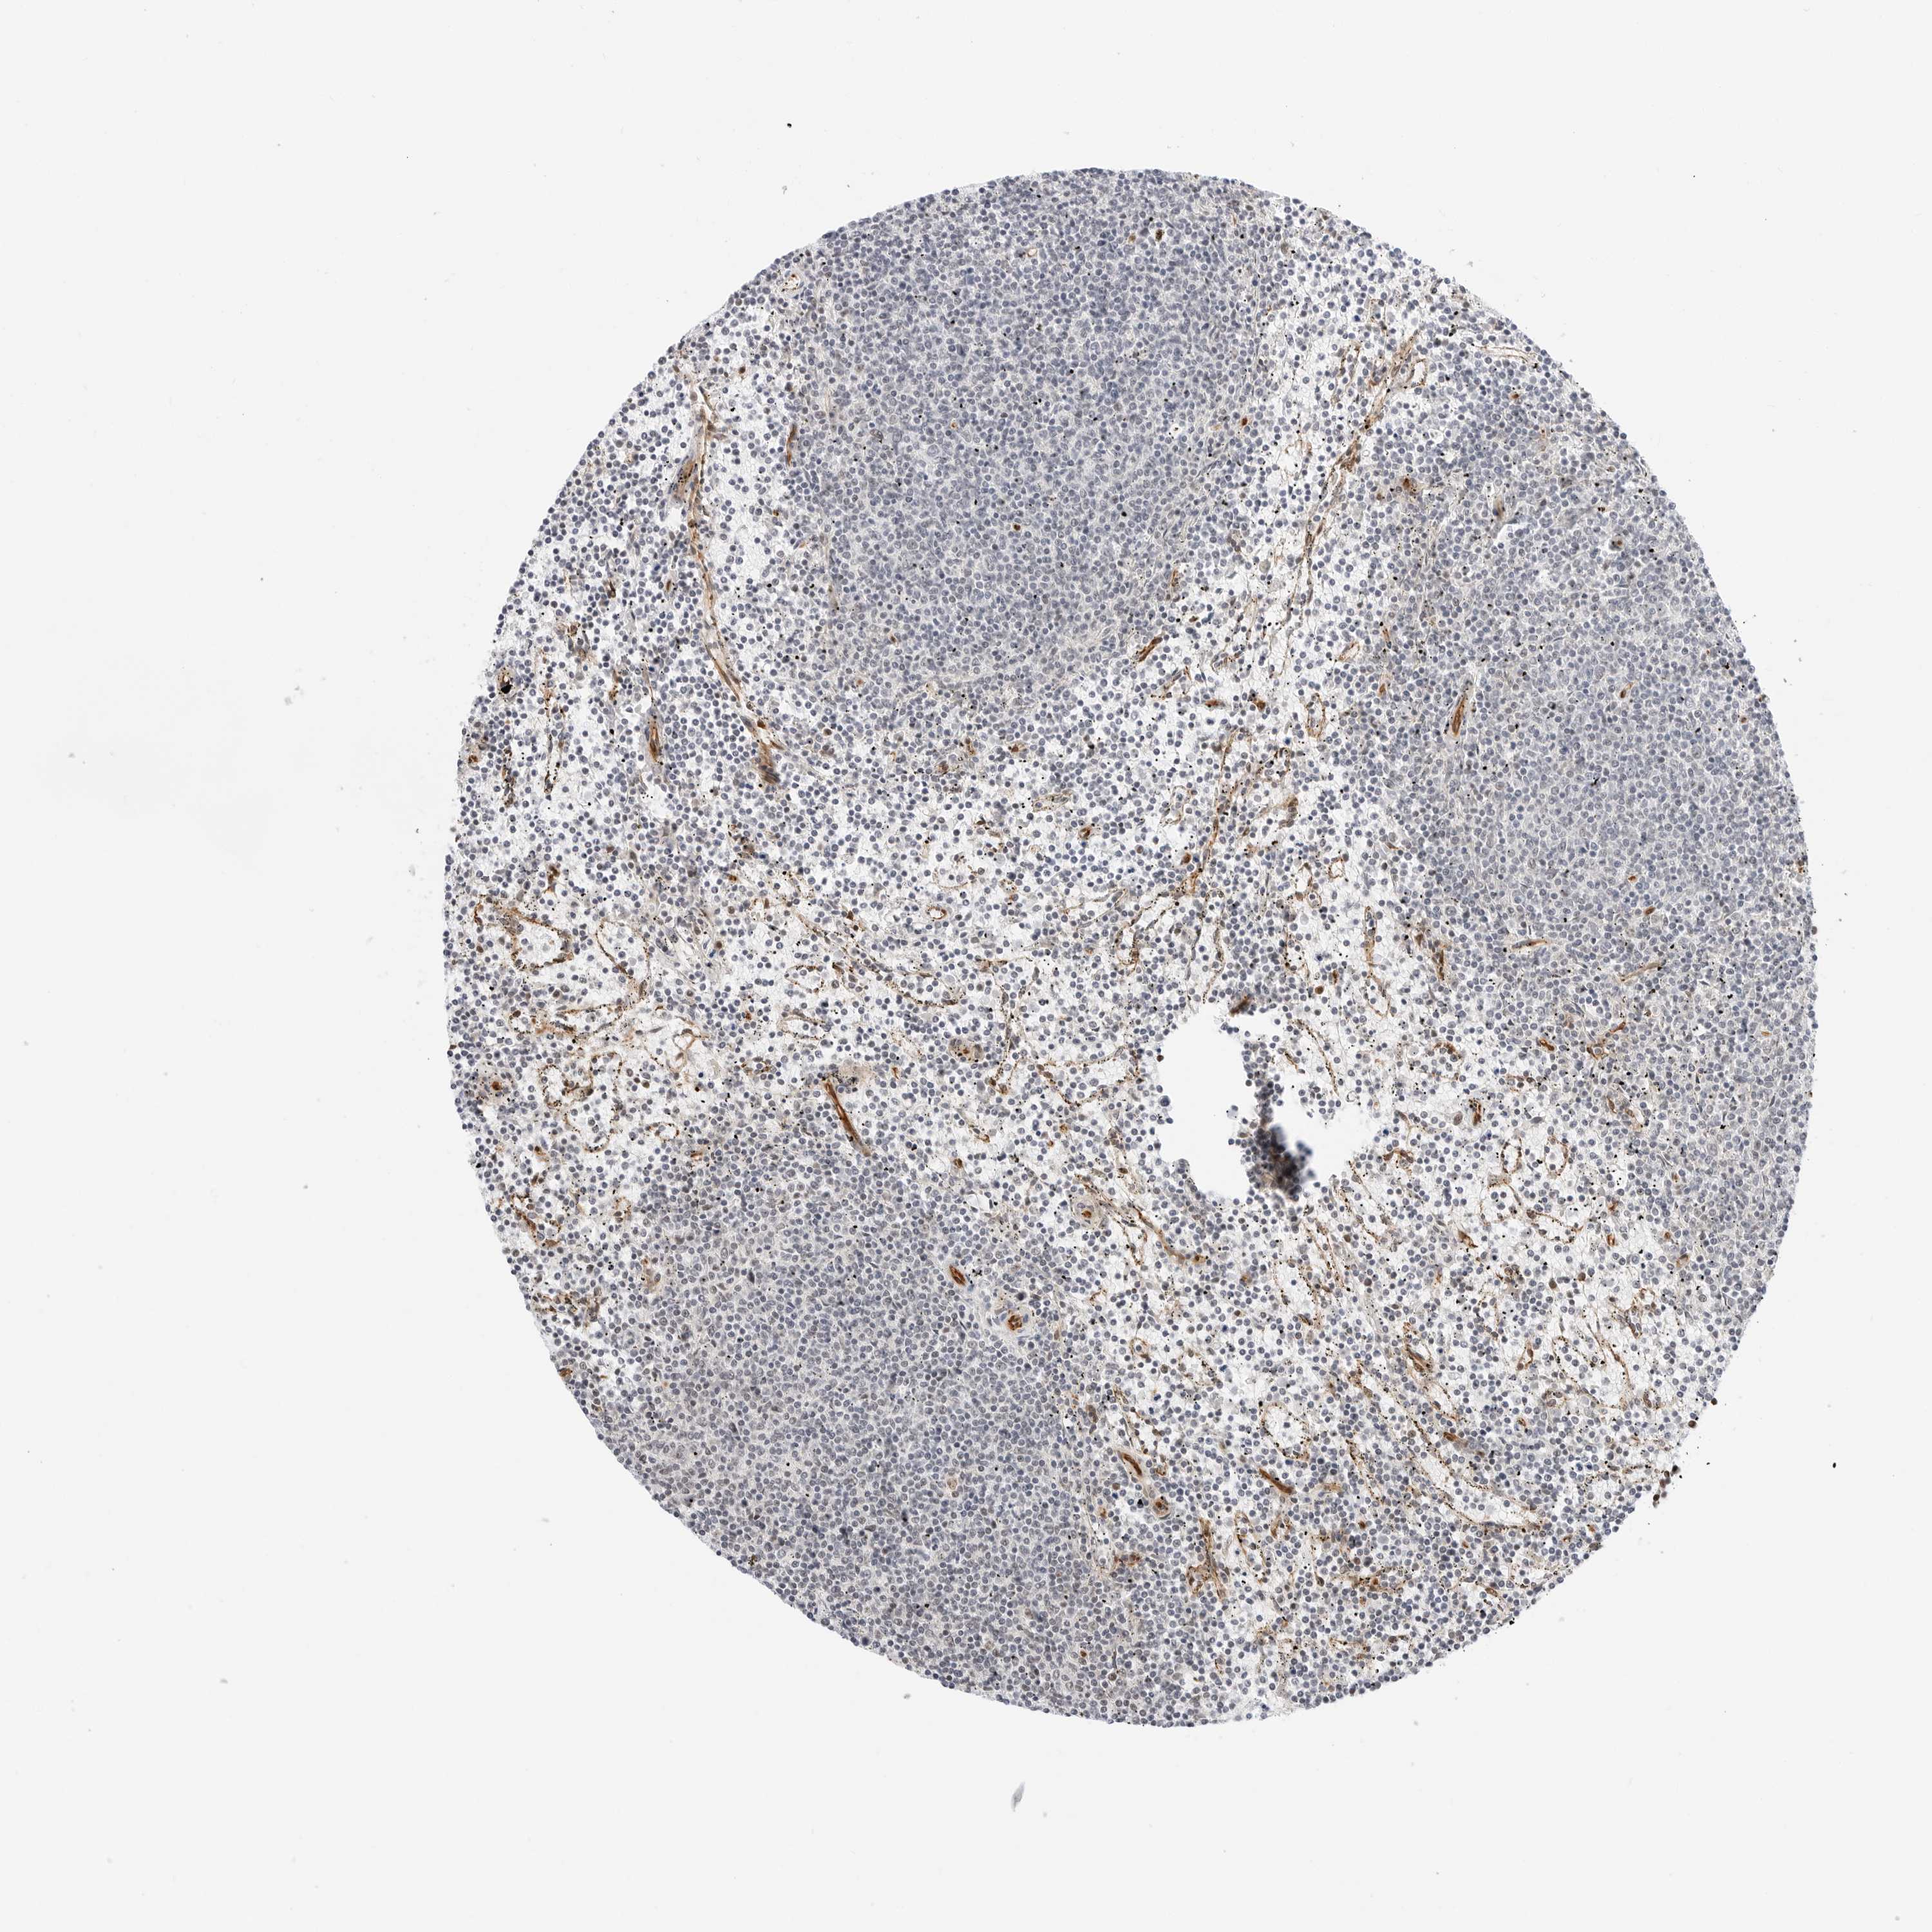

CANCER LYMPHOMA Show tissue menu

LYMPHOMA - Protein expressioni

A mouse-over function shows sample information and annotation data. Click on an image to view it in a full screen mode. Samples can be filtered based on level of antibody staining by selecting one or several of the following categories: high, medium, low and not detected. The assay and annotation is described here.

Each image is clickable and will lead to virtual microscopy that enables deeper exploration of all samples and also displays staining intensity scores, fraction scores and subcellular localization as well as patient and tissue information for each sample.

Antibody HPA026833

Staining

Medium

Weak

<25%

Location

Cytoplasmic/membranous

Hodgkin's disease, NOS

Malignant lymphoma, non-Hodgkin's type, High grade

Malignant lymphoma, non-Hodgkin's type, Low grade